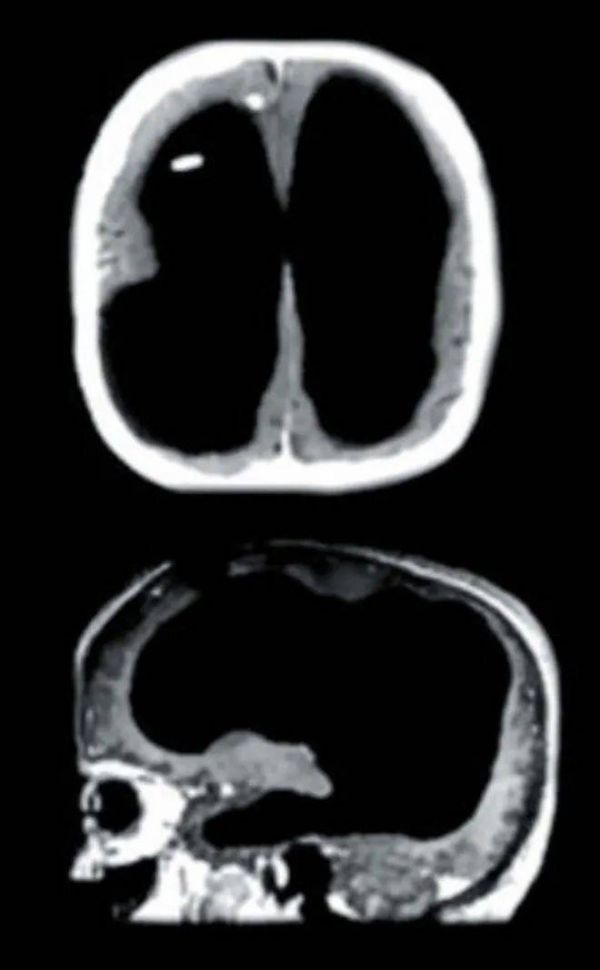

没有大脑组织的头骨内部。© Wikimedia Commons

正常人的大脑皮层厚度一般为4.5厘米,但他只有薄薄的1毫米,剩下的部分充满了水样脑脊液。这一现象可能是因为脑脊液不断积蓄,导致颅内压升高、颅内空间减少,因此大脑皮层向外侧(即向头骨)填充发育缓慢。这也就意味着,大脑皮层沟回越深,发育期间越不受压制,脑结构相对而言就越完整(尽管大脑皮层在压力下仍会收缩,也可能达不到正常状态)。

约翰·洛伯对脑水肿患者脑部的扫描图。© CRÓNICA